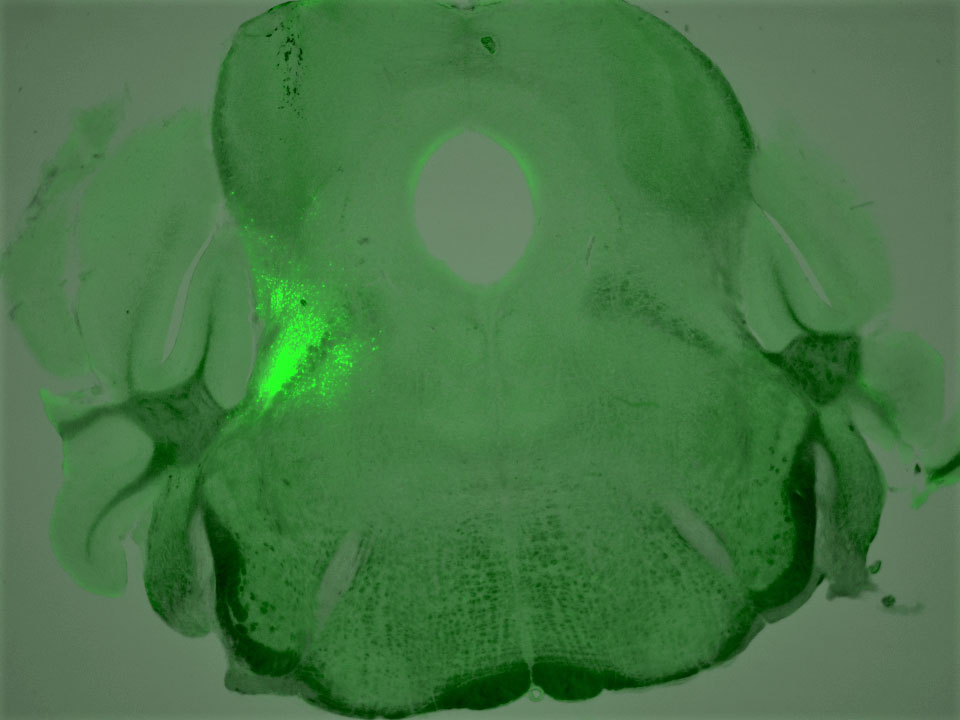

Excited to share our new story on the neural circuits that coordinate breathing, pain, and emotion! Big thanks to Sung @iamhans and my wonderful co-authors including @neuron_MY @PLURplus @SJ_J_Kang_24! Short thread below👇(1/n)

Our paper on pain-breathing interaction is out today. Kudos to everyone involved! Especially @ShijiaLiu1 for her hard work and perseverance. bit.ly/3IXsuFo

Salk #neuroscientists in @iamhans's lab with first-author @ShijiaLiu1 have discovered that blocking opioid receptors in specific neurons can restore breathing during an overdose.

salk.edu/news-release/r…